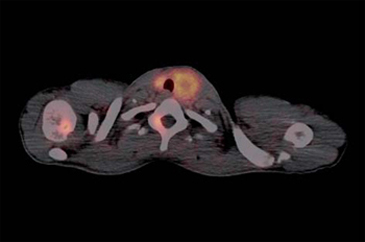

Cáncer medular de tiroides

El tumor medular de tiroides es una neoplasia poco frecuente (3-5% de todos los cánceres de tiroides) proveniente de las células C parafoliculares (Figuras 6 y 7). La mayoría ocurre en forma esporádica (70-80% de los casos) pero existen formas familiares (solos o como parte del síndrome NEM 2A y 2B)20. Este tumor metastiza precozmente a los ganglios cervicales (55-75% de los casos), principalmente el compartimiento central del cuello. Metástasis a distancia se encuentran en 10-15% de los pacientes, principalmente mediastino, pulmones, hígado y hueso21 (Figuras 8 y 9). Debido a la producción de calcitonina por las células C, esta hormona es usada como marcador tumoral al diagnóstico y durante el seguimiento. La resección quir úrgica completa (tiroidectomía total y disección cervical amplia) es la únicaforma de curación. A pesar de la agresividad de este tratamiento, 40% de los pacientes operados mantienen niveles de calcitonina medibles y otro 10% inicialmente negativo, recurrirá en el tiempo2. Por esta razón, la localización de cualquier cúmulo tumoral existente mediante imágenes es de extrema importancia. Los criterios usados en imágenes diagnósticas para el tumor primario son similares a los usados en el cáncer diferenciado de tiroides, sin embargo, la localización de adenopatías y metástasis a distancia es generalmente difícil22. Convencionalmente se ha usado ecografía, tomografía computada y cintigrafía (In111-pentatreotide, Tc99m-DMSA- V y Tc99m-MIBI) para evaluar pacientes con enfermedad recurrente. Tc99m(V)-DMSA (ácido dimercaptosuccínico pentavalente) es un marcador tumoral inespecífico. El mecanismo de captación es sólo parcialmente conocido y tendría relación con la presencia de grupos fosfatos y el pH del medio. Su uso en esta enfermedad fue descrito por primera vez en 1984 por Ohta23. La sensibilidad reportada de la cintigrafía con DMSA-V se encuentra entre 50-80% y su uso combinado con In111- pentatreotide alcanza 86%24. F18-FDOPA es un aminoácido (dihidroxifenilalanina) marcado con Flúor18 usado originalmente para el estudio de pacientes con enfermedad de Parkinson. Los tumores neuroendocrinos pueden captar y decarboxilar p recursores de aminoácidos tales como la DOPA y ser visualizados con PETFDOPA. Las series reportan sensibilidades entre 44 y 90% para este método2. Desafortunadamente para la síntesis de F18-FDOPA se requiere de blancos especiales en el ciclotrón (diferentes a los usados para la producción de FDG) y de módulos de síntesis dedicados, lo que hace que este radiofármaco aún no esté disponible en nuestro medio. Si bien el 85% de los tumores medulares de tiroides expresan algún tipo de receptores de somatostatina y 75% expresan los tipos 2,3 ó 5 (que son los afines por octreotide), el subtipo 2 es expresado sólo en 43%25, que es el blanco principal de los análogos disponible para imagen y terapia. La afinidad de estas moléculas por los subtipos 3 y 5 es típicamente menor. Esto explica la variabilidad de resultados en la literatura en relación con la sensibilidad tanto de la cintigrafía con In111-pentatreotide (Octreoscan) como para el PET con derivados de la somatostatina para la detección de esta neoplasia. Las series publicadas con In111-pentatreotide reportan sensibilidades entre 50-75% para cáncer medular de tiroides y sugieren que este método es mejorpara metástasis ganglionares en el cuello o mediastino que para metástasis a distancia2. Estudios con PET y análogos de somatostatina son escasos para esta enfermedad. La limitada información disponible sugiere que la sensibilidad de PET-análogos de somatotatina es inferior al PET-FDOPA en cáncer medular de tiroides tanto a nivel de paciente como de lesión y similar a los resultados de estudios realizados con PET-FDG. En el trabajo retrospectivo de Conry et al2, se estudiaron 18 pacientes con recidiva de cáncer medular de tiroides a los que se le realizó PET con Ga68-DOTATATE y F18-FDG. La sensibilidad encontrada por paciente fue 72% para DOTATATE y 78% para FDG. FDG encontró 28 metástasis mientras que DOTATATE 23. Treglia et al26 recientemente publicó una serie prospectiva de 18 pacientes con recurrencia de cáncer medular de tiroides estudiados PET y Ga68-análogos de somatostatina, F18-FDOPA y F18-FDG. En este trabajo la sensibilidad por paciente fue 72% para FDOPA, 33% para análogos de somatostatina y 17% para FDG. A nivel de lesiones la sensibilidad fue: 85% para FDOPA, 20% para análogos de somatostatina y 28% para FDG.